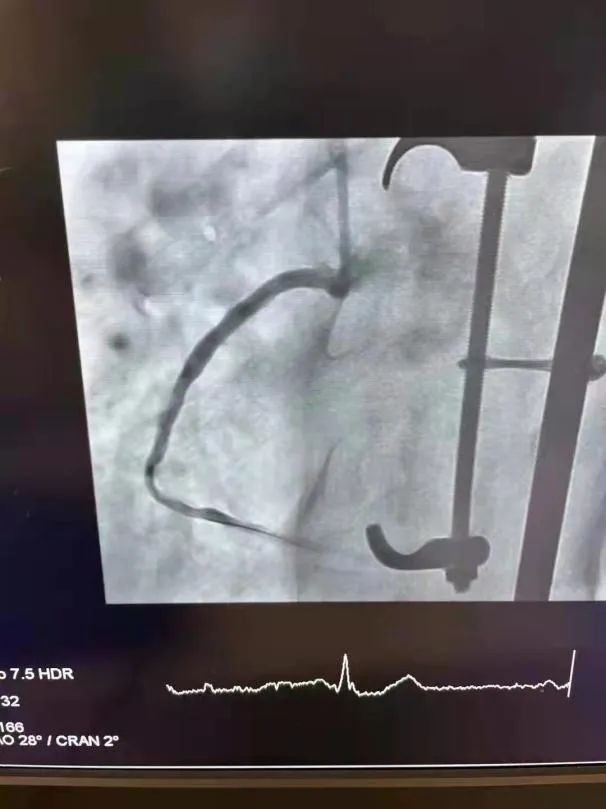

图片

植入HT Supreme支架前